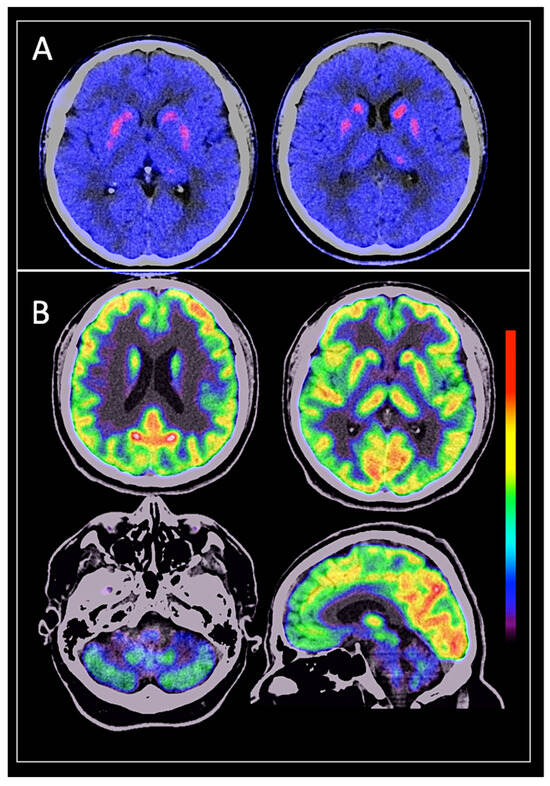

3.2. Brain [18F]DOPA PET/CT Findings

3.3. Brain [18F] FDG PET/CT Findings